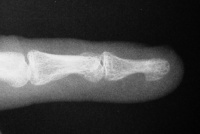

| Case 1. 6 week old grossly unstable distal phalanx fracture. Fracture reduced through a midline palmar approach and stabilized with extraarticular nonparallel Kirschner wires. |